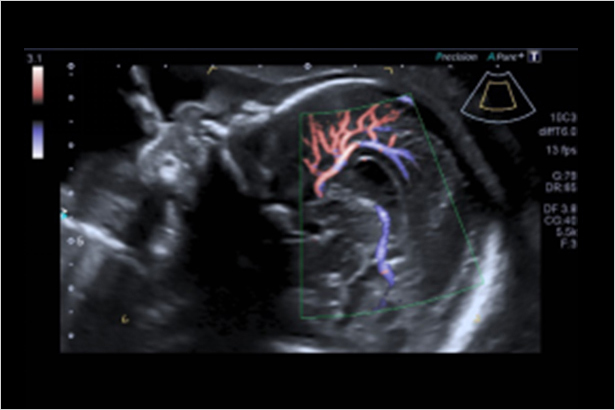

SMI帶來精細和清晰的彩色多普勒血流成像。SMI擴展了可見血流的范圍。低速微血流,SMI可以呈現

可同時顯示大血管內血流方向信息以及微灌注信息